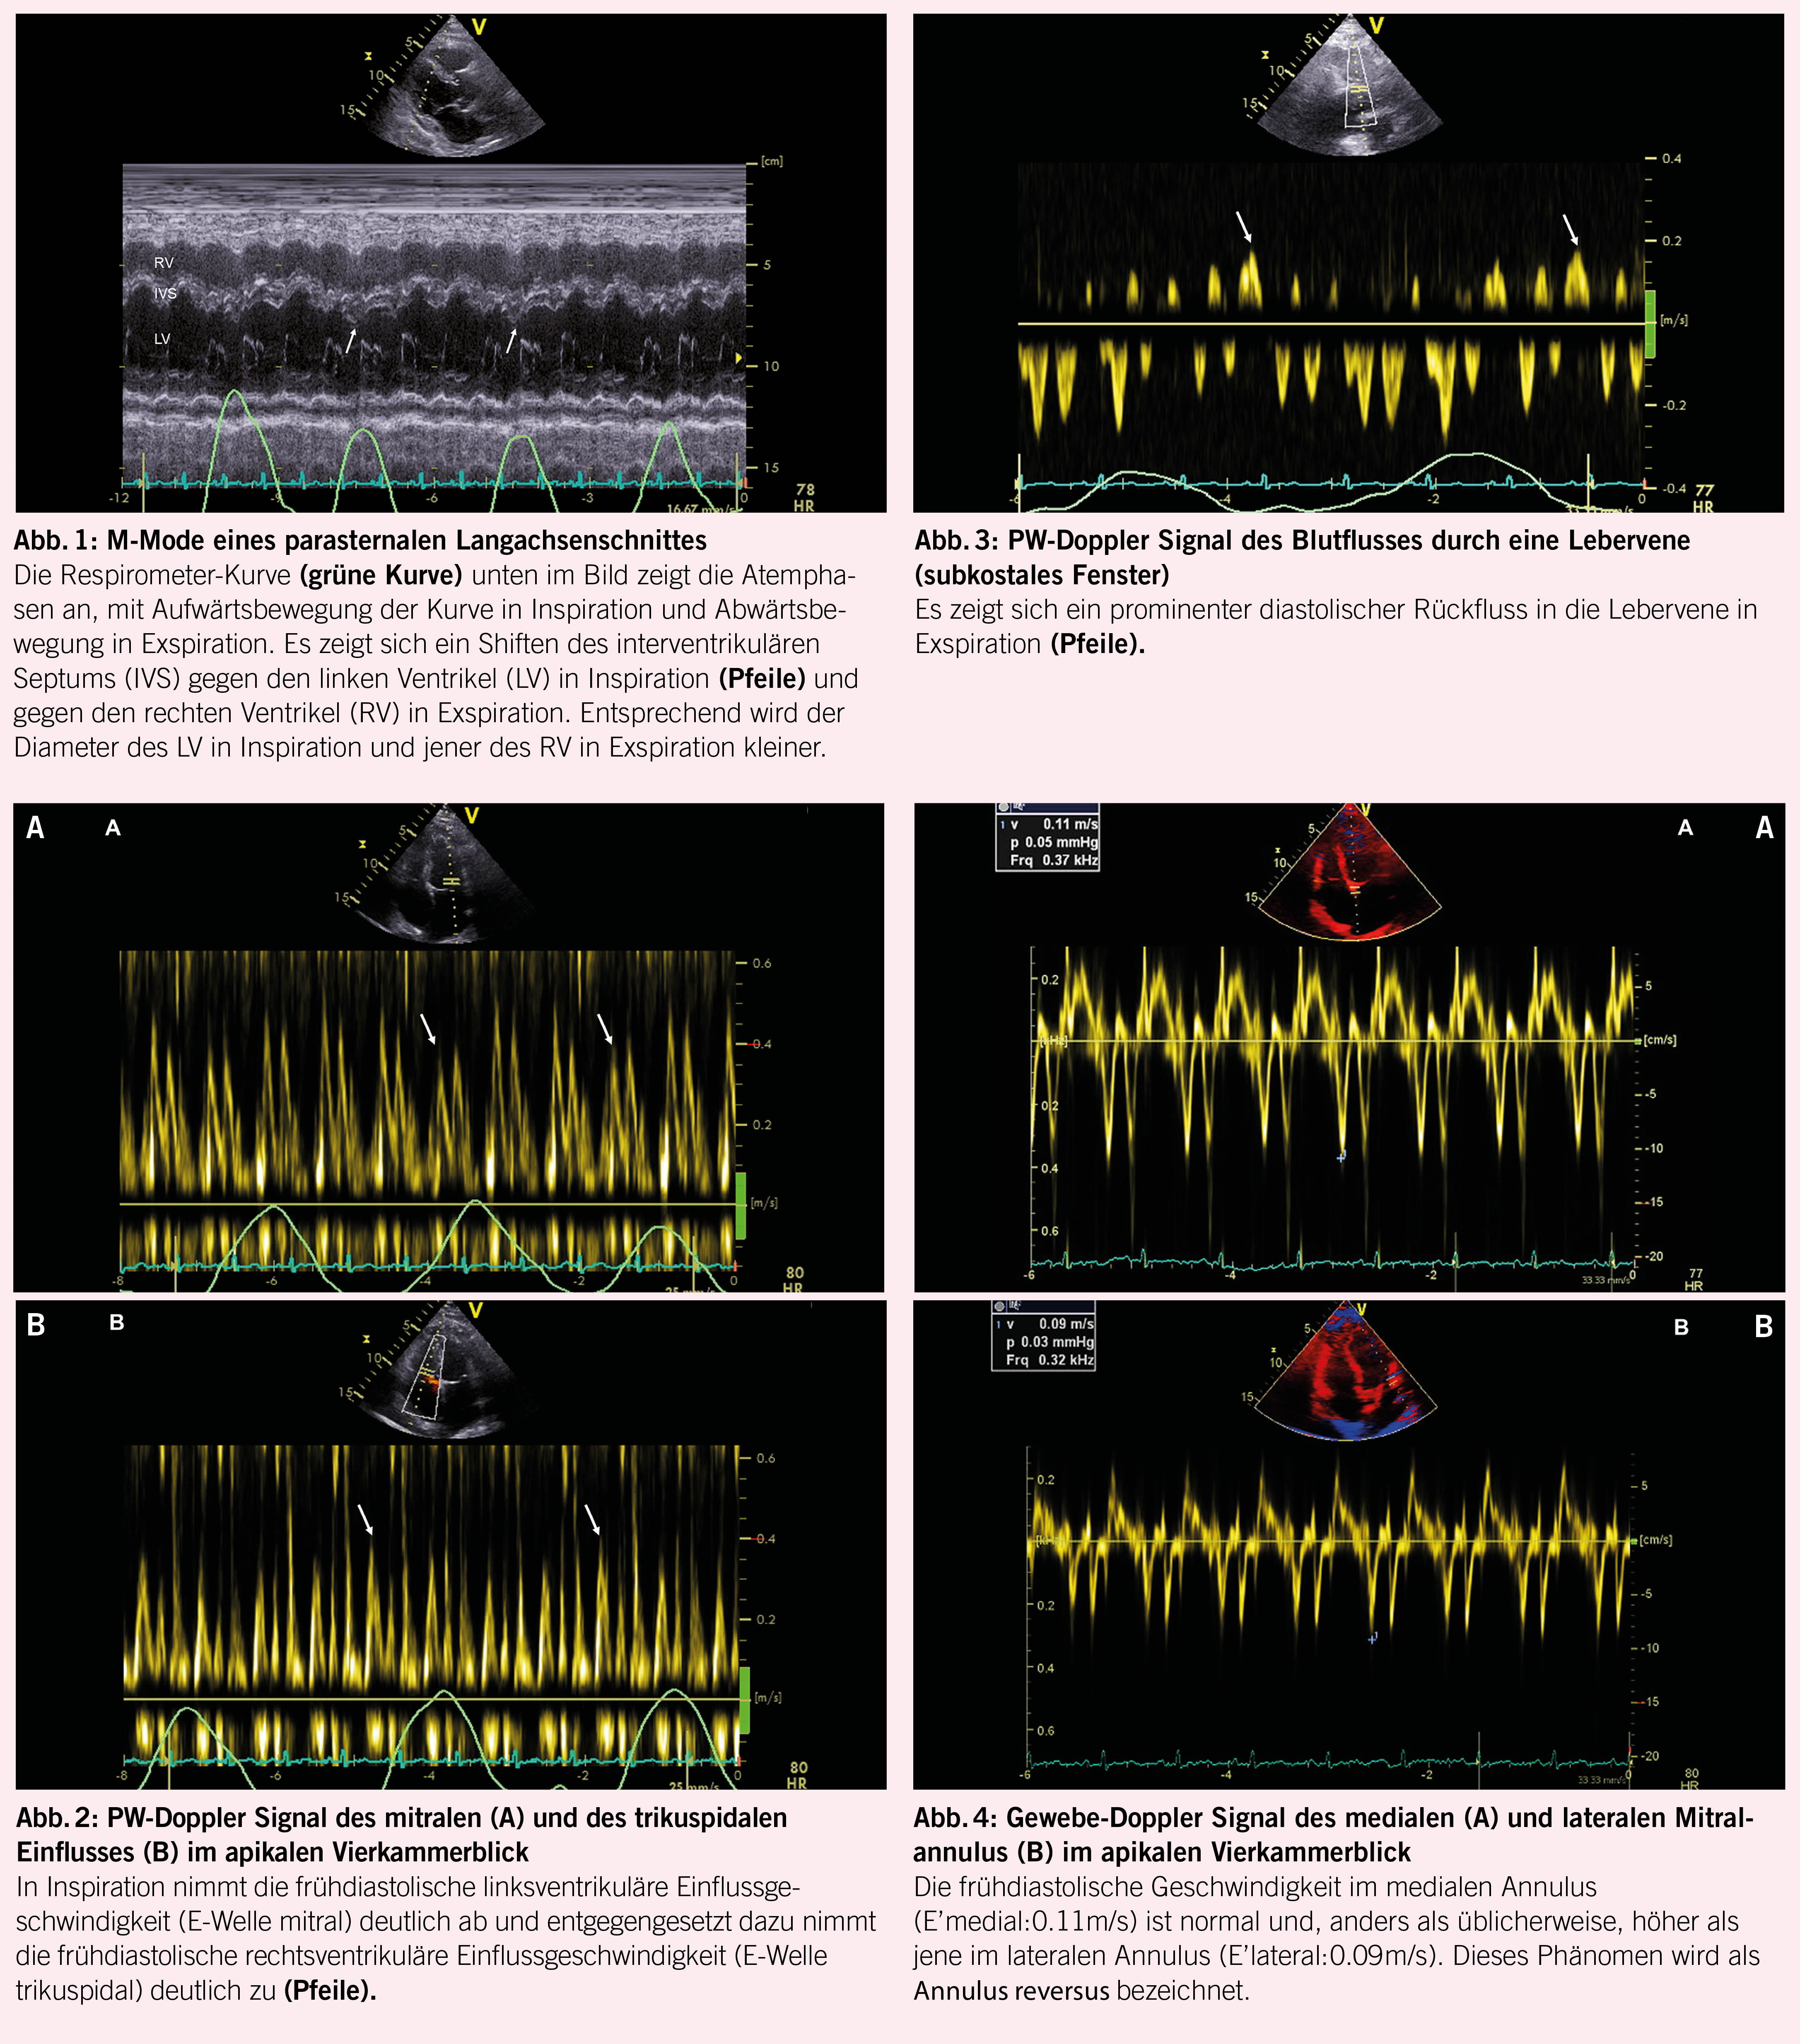

Ein 65-jähriger Patient klagte in den vergangenen Monaten über eine zunehmende Dyspnoe. Diese ging mit einer progredienten Müdigkeit einher. Im Verlauf kam es auch zu zunehmenden Unterschenkelödemen und zu einem Druck im Oberbauch. Im Rahmen der Abklärungen wurde eine transthorakale Echokardiographie durchgeführt. Sowohl die linksventrikuläre, als auch die rechtsventrikuläre systolische Funktion erwiesen sich dabei als normal. Es fiel jedoch eine atemvariable Bewegung des interventrikulären Septums auf, mit einem Shift des Septums gegen den linken Ventrikel in Inspiration und gegen den rechten Ventrikel in Exspiration, was besonders gut im M-Mode des parasternalen Langachsenschnittes dargestellt werden konnte (Abb. 1). Ebenfalls zeigte sich im PW-Doppler eine Atemvariabilität der Einflussmuster durch die AV-Klappen, mit Abnahme der transmitralen E-Welle in Inspiration und Zunahme in Exspiration (Abb. 2A) und entgegengesetztem Verhalten der transtrikuspidalen E-Welle (Abb. 2B). In der PW-Doppler Untersuchung einer Lebervene konnte ein prominentes diastolisches Rückfluss-Signal in Exspiration dargestellt werden (Abb. 3). Im Gewebe-Doppler des medialen und lateralen Mitralklappenannulus zeigten sich erhaltene frühdiastolische Geschwindigkeiten (E’), wobei das me-diale E’ (Abb. 4A) höher war als das laterale E’ (Abb. 4B). Die Doppler-echokardiographisch erhobenen Befunde waren klassisch für das Vorliegen einer Pericarditis constrictiva. Der Patient wurde nach Vervollständigung der Abklärungen einer Perikardektomie unterzogen, was im Verlauf zur deutlichen Reduktion seiner Beschwerden führte.

Die Doppler-Echokardiographie ist in der Lage, diese pathophysiologischen Veränderungen aufzuzeigen. Als nützliche und indikative echokardiographische Parameter erweisen sich bei der Pericarditis constrictiva das respiratorische Shiften des ventrikulären Septums, in Inspiration gegen den linken, in Exspiration gegen den rechten Ventrikel (Abb. 1) (4), die Abnahme der transmitralen E-Welle und die Zunahme der transtrikuspidalen E-Welle in Inspiration (Abb. 2A und B) (4, 5), der exspiratorisch betonte diastolische Rückfluss im PW-Doppler Signal der Lebervenen (Abb. 3) (5), die erhaltene oder akzentuierte frühdiastolische Gewebe-Doppler Geschwindigkeit im medialen Mitralannulus (E’ medial; Abb. 4A) (6) und der sogenannte Annulus reversus, d.h. das Vorliegen eines gleich hohen oder höheren E’ im medialen verglichen zum lateralen Annulus (Abb. 4A und B) (7). Letzteres Phänomen kommt durch das Tethering des lateralen Annulus infolge des konstriktiven perikardialen Prozesses zustande.

Gemäss einer Studie der Mayo-Clinic scheinen der respiratorische Shift des interventrikulären Septums, das erhaltene oder erhöhte mediale E’ und das exspiratorisch betonte diastolische Backflow-Signal in den Lebervenen am engsten mit der Diagnose der Pericarditis constrictiva assoziiert zu sein (3).